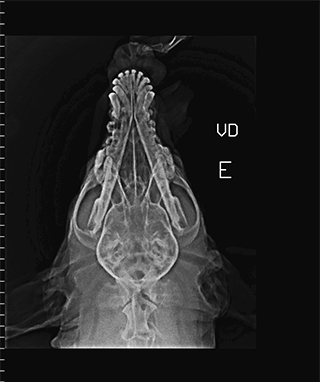

Radiologia Digital Direta / Digital Radiography

As radiografias geradas digitalmente podem ser transmitidas para iPad Apple®, notebooks e smartphones.

iPad com tela Retina Apple® possibilita a visualização das imagens com maior qualidade diagnóstica.

O treinamento aborda a geração das radiografias, a edição digital das imagens, e também a

escolha adequada de técnicas radiográficas como kilovoltagem, corrente elétrica e tempo de exposição.